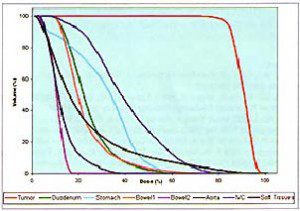

Τα παραδοσιακά συστήματα ακτινοθεραπείας στοχεύουν στη βλάβη από έναν σχετικά μικρό αριθμό σταθερών θέσεων. Αντίθετα, στην ρομποτική ακτινοχειρουργική με CyberKnife® επιλέγονται από το σύστημα εκατοντάδες γωνίες ακτινοβόλησης, που επιλέγονται ανάμεσα σε μερικές χιλιάδες θέσεις που υποστηρίζει το σύστημα. Έτσι έχουμε δυνατότητα να δώσουμε μεγάλες δόσεις θεραπείας στο στόχο στο πάγκρεας, επιβαρύνοντας ελάχιστα τους γύρω φυσιολογικούς ιστούς.

Τα παραδοσιακά συστήματα ακτινοθεραπείας στοχεύουν στη βλάβη από έναν σχετικά μικρό αριθμό σταθερών θέσεων. Αντίθετα, στην ρομποτική ακτινοχειρουργική με CyberKnife® επιλέγονται από το σύστημα εκατοντάδες γωνίες ακτινοβόλησης, που επιλέγονται ανάμεσα σε μερικές χιλιάδες θέσεις που υποστηρίζει το σύστημα. Έτσι έχουμε δυνατότητα να δώσουμε μεγάλες δόσεις θεραπείας στο στόχο στο πάγκρεας, επιβαρύνοντας ελάχιστα τους γύρω φυσιολογικούς ιστούς.